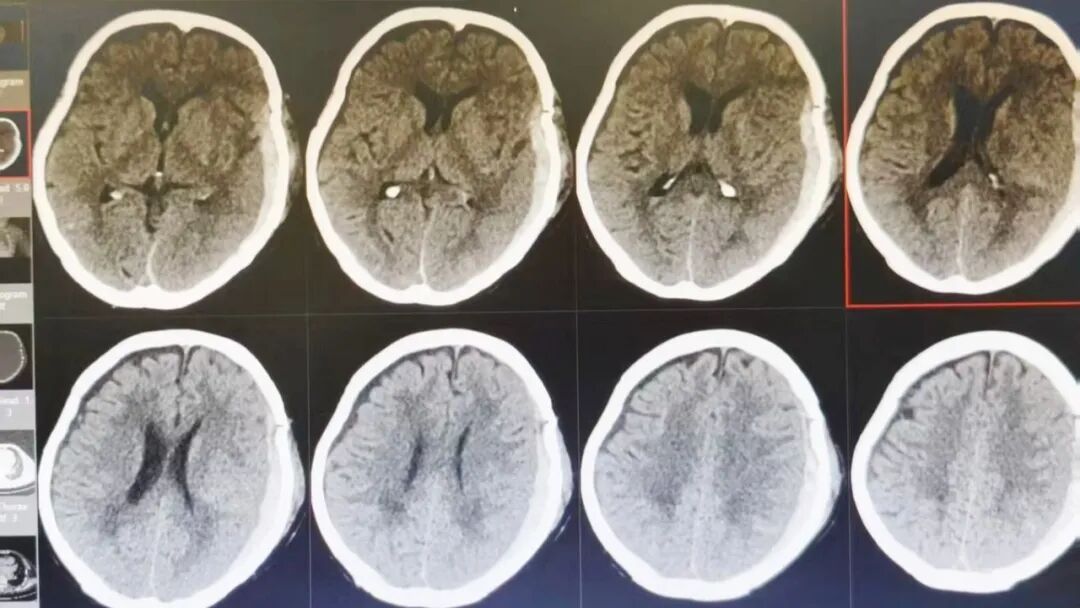

89 岁的吴阿婆(化名)突发意外,被发现时已意识不清、陷入昏迷。家人发现后,紧急将其送往漳州第三医院,检查结果令人揪心:重型颅脑损伤、脑内大面积出血,加之 O 型 Rh(D) 阴性熊猫血、严重贫血······多重致命高危因素叠加,病情十分危重。

如此复杂凶险的状况,在常人看来几乎已是绝境!但漳州第三医院神经外科团队没有放弃,考虑到阿婆身体条件极差、血型特殊、手术风险难以预估,最终摒弃常规开颅方案,为她量身制定了个体化精准保守治疗方案,在绝境中为生命守住一线希望。